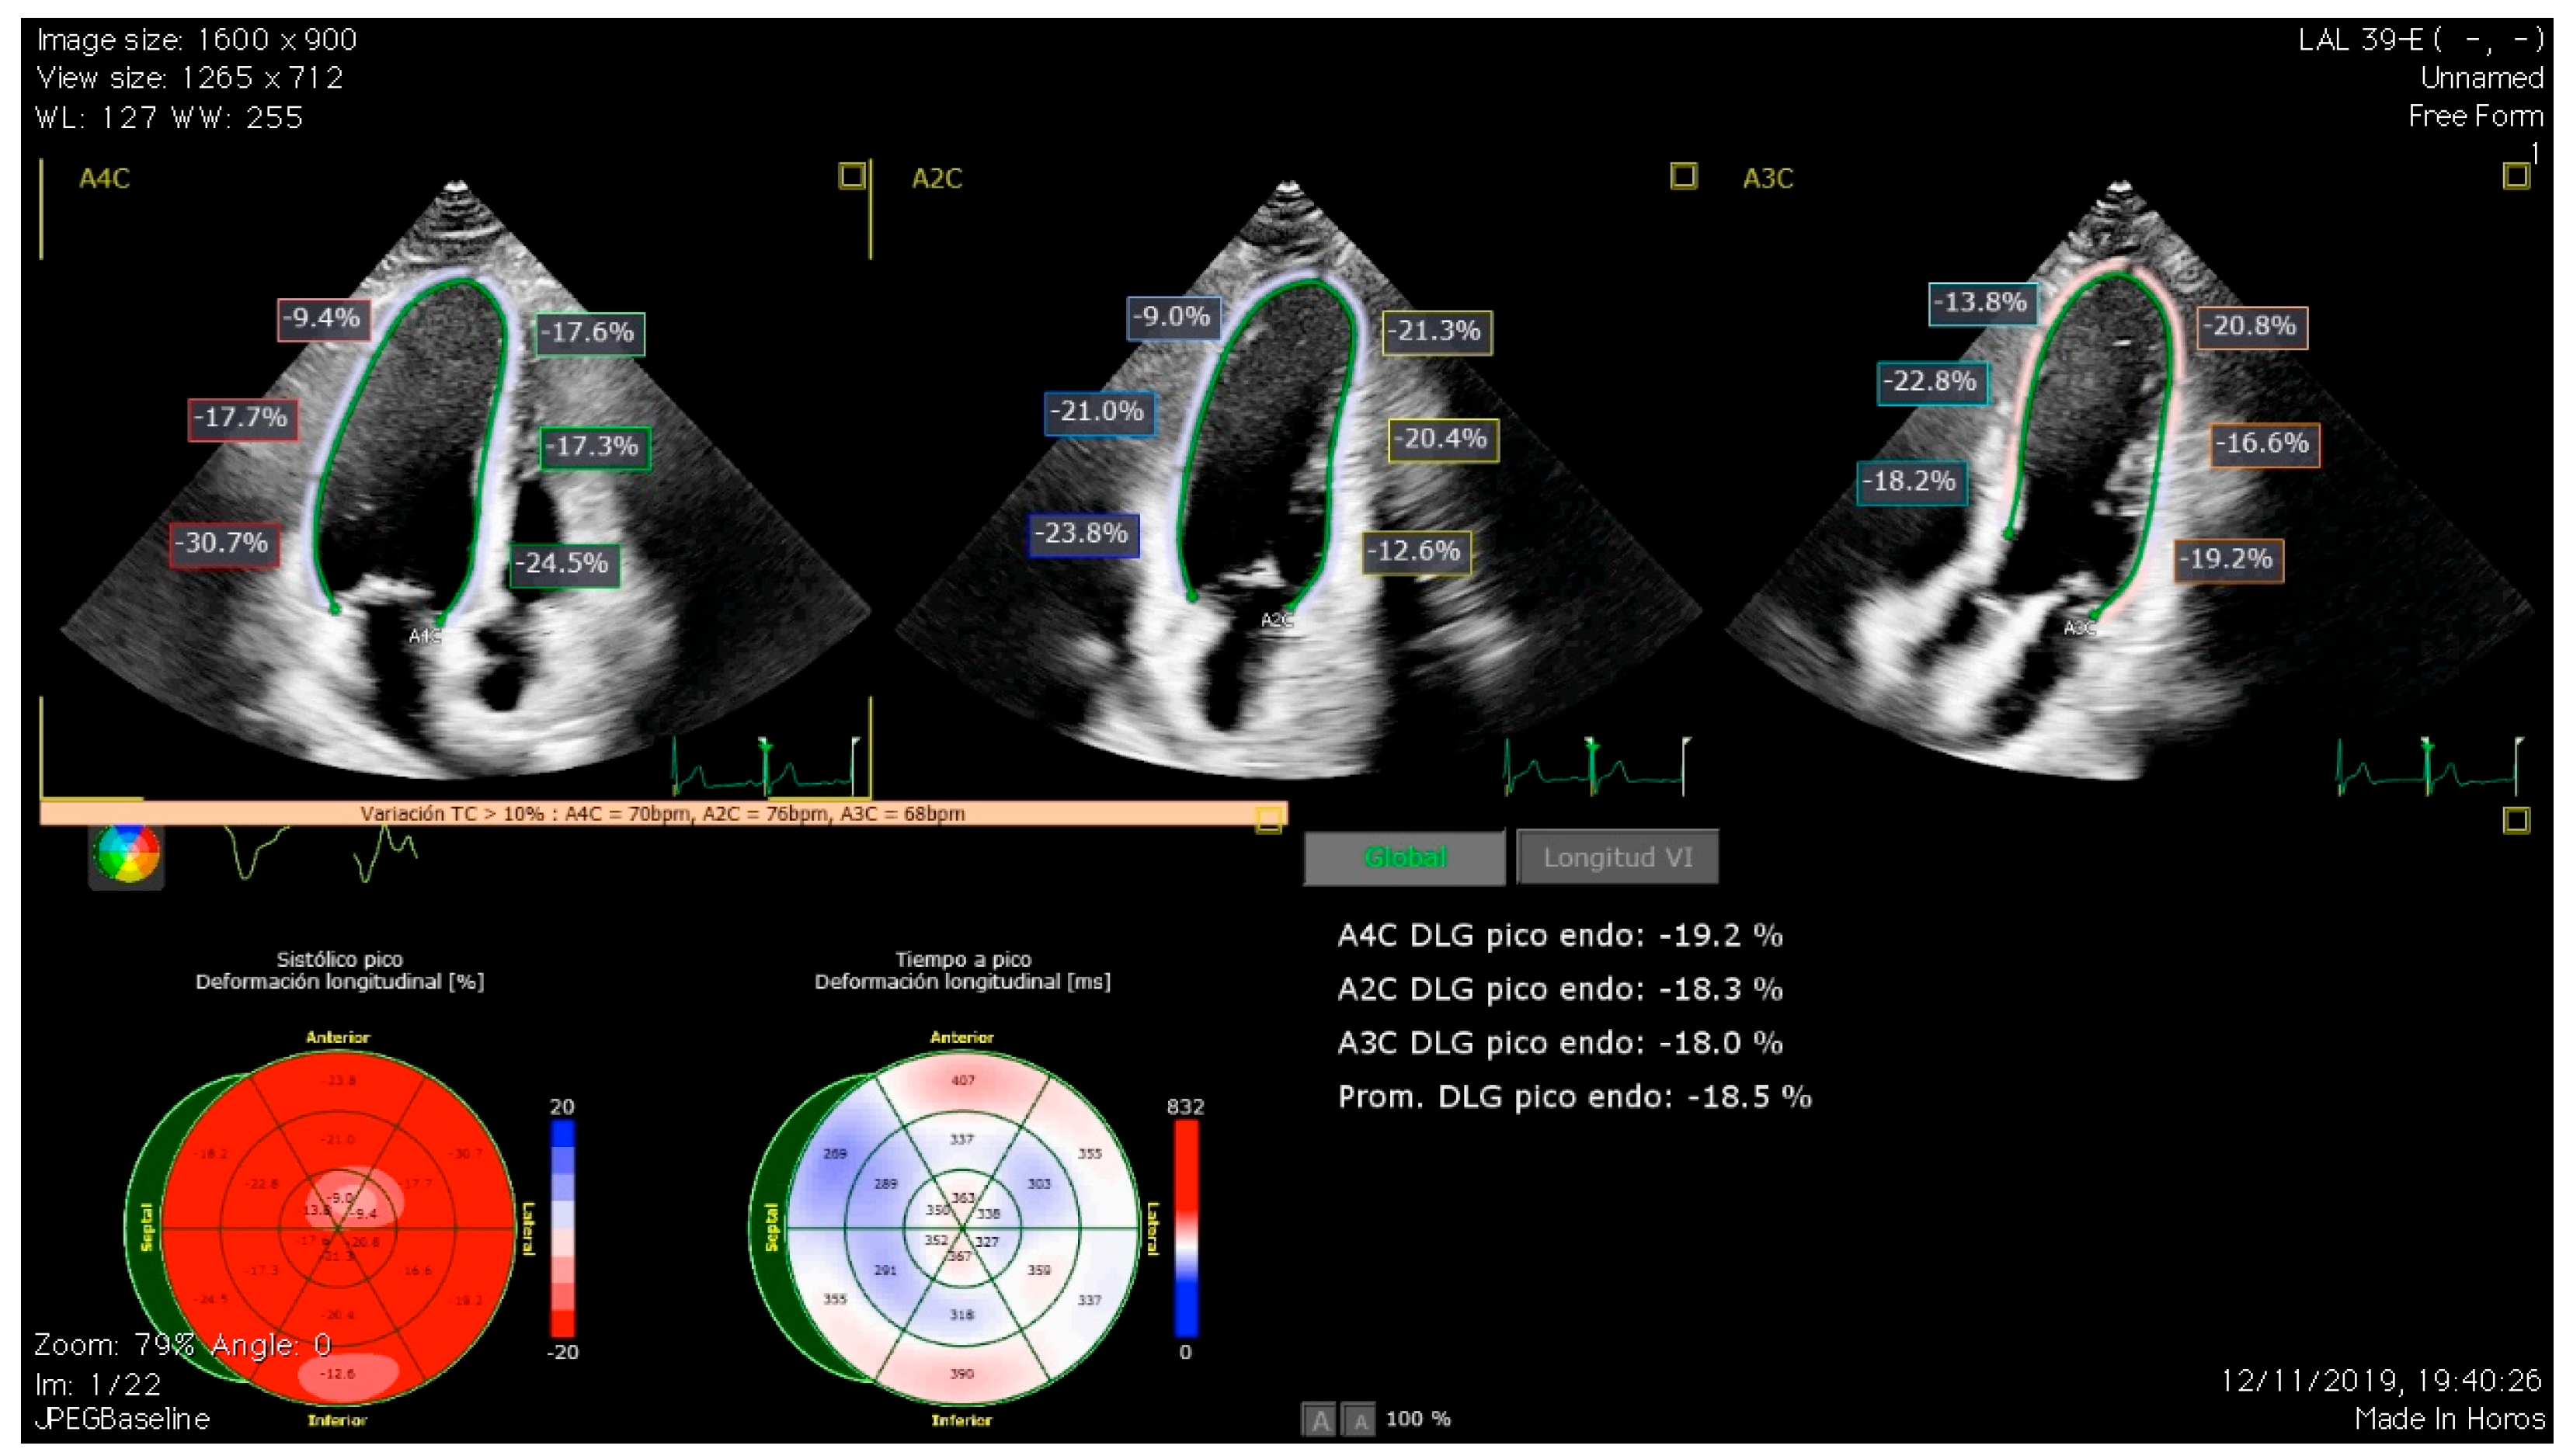

The importance of GLS relies on its ability to detect subclinical dysfunction, given its high sensitivity in the detection of changes in the deformation of longitudinal myocardial fibers (Figure 1). There are multiple studies that have proven its value in the assessment of cardiotoxicity [23]. In line with this, our group recently investigated the role of GLS in detecting subclinical LVSD in a cohort of long-term childhood leukemia survivors, finding abnormal GLS values in up to 26% of the survivors [14]. Later, we evaluated LV diastolic function using conventional parameters and left atrial strain (LAS), finding an association between incremental doses of anticancer treatments and LAS impairment and displaying LAS as a potential early marker of diastolic dysfunction in these patients [24]. LAS is a relatively novel echocardiographic parameter with good sensitivity and specificity in the assessment of LV diastolic function and has shown a good correlation with invasive techniques for the assessment of filling pressures [25]. All the evidence previously exposed on the diagnosis of CTRCD revolves around the evaluation of LV function. Nevertheless, patients exposed to chemotherapy are not exempt from suffering right ventricle (RV) dysfunction. Evaluation of RV systolic function can be challenging due to its intricate geometry, and, in this aspect, RV strain has become a useful tool as it showed a better correlation with RV ejection fraction than other traditional parameters [26]. The role of RV strain measurement and the significance of RV impairment in terms of prognosis is not clearly established. Our research group reported a decrease in CCS RV strain that was inversely associated with modifiable ca and smoking habit [27]. Abnormal values of RV strain have also been reported in other cohorts of long-term CCS. However, further longitudinal studies are needed to clarify the prognostic value of this finding [28].

Figure 1.

Global longitudinal strain (GLS) assessment in a long-term survivor of childhood cancer using automated software (QLAB 15.0., Philips Medical Systems, Andover, MA, USA). The upper panels show automatic segment quantification of GLS by speckle tracking in the four-chamber, two-chamber, and three-chamber views. The lower panels show GLS values in the bull’s eye plot and average values of GLS.